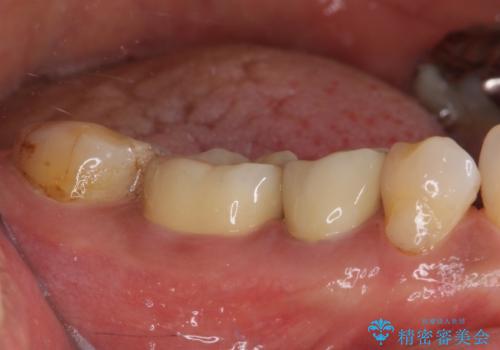

高強度のジルコニアクラウンとしたことで、強い咬合力でも壊れず、審美性を維持しやすい治療を行うことができました。